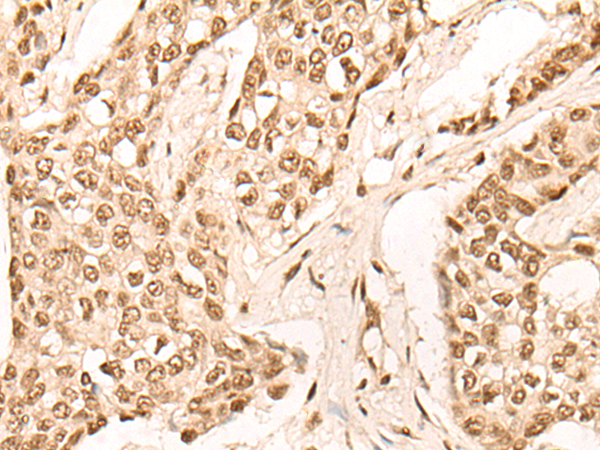

IHC positive control: |

Human esophagus cancer and Human breast cancer |

IHC Recommend dilution: |

50-300 |